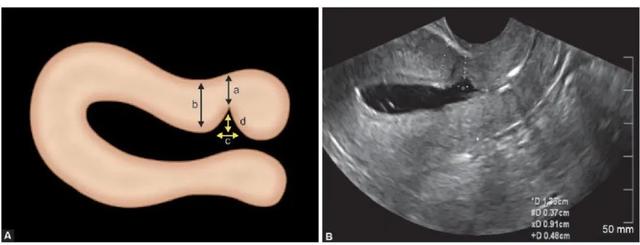

对于手术,我们老百姓有个俗称,叫「开刀」。既然是开刀自然会有一个切口,当剖宫产术后的子宫切口愈合缺陷时,切口处会出现一个与宫腔相通的凹陷,看起来好像一道沟,这个凹陷就是我们所说的憩室。

剖宫产术后子宫切口憩室 (preꦿvious cesareanscar defect,PCSD )以往报道较少 ,1955 ♛年西班牙学者首次报道了子宫切口憩室。由于它是在剖宫产后出现,所以被称为剖宫产术后子宫切口憩室,又俗称为剖宫产瘢痕憩室。

子宫切口憩室多位于子宫下段或峡部,少数位于宫颈上段,主要与原剖宫产切口部位及剖宫产时临♌床宫颈有无缩短或扩展有🅰关,简单点说,它就像一间违章改建的“危房”。

近年来,随着宫腔镜的普及,宫腔镜手术治疗PCSD陆续有报道 ,且有成为治疗PCSD 首选手术方法的趋势。

目前手术方法是应用宫腔镜电切切口下缘疤痕组织并电凝憩室创面,简单点说,就好像我们修补衣服一样,把原来的大疙瘩剪掉,重新尽可🐲能让切口变得平整。另外两种治疗方法用得比较少,这里飒姐就不赘述🅘了。